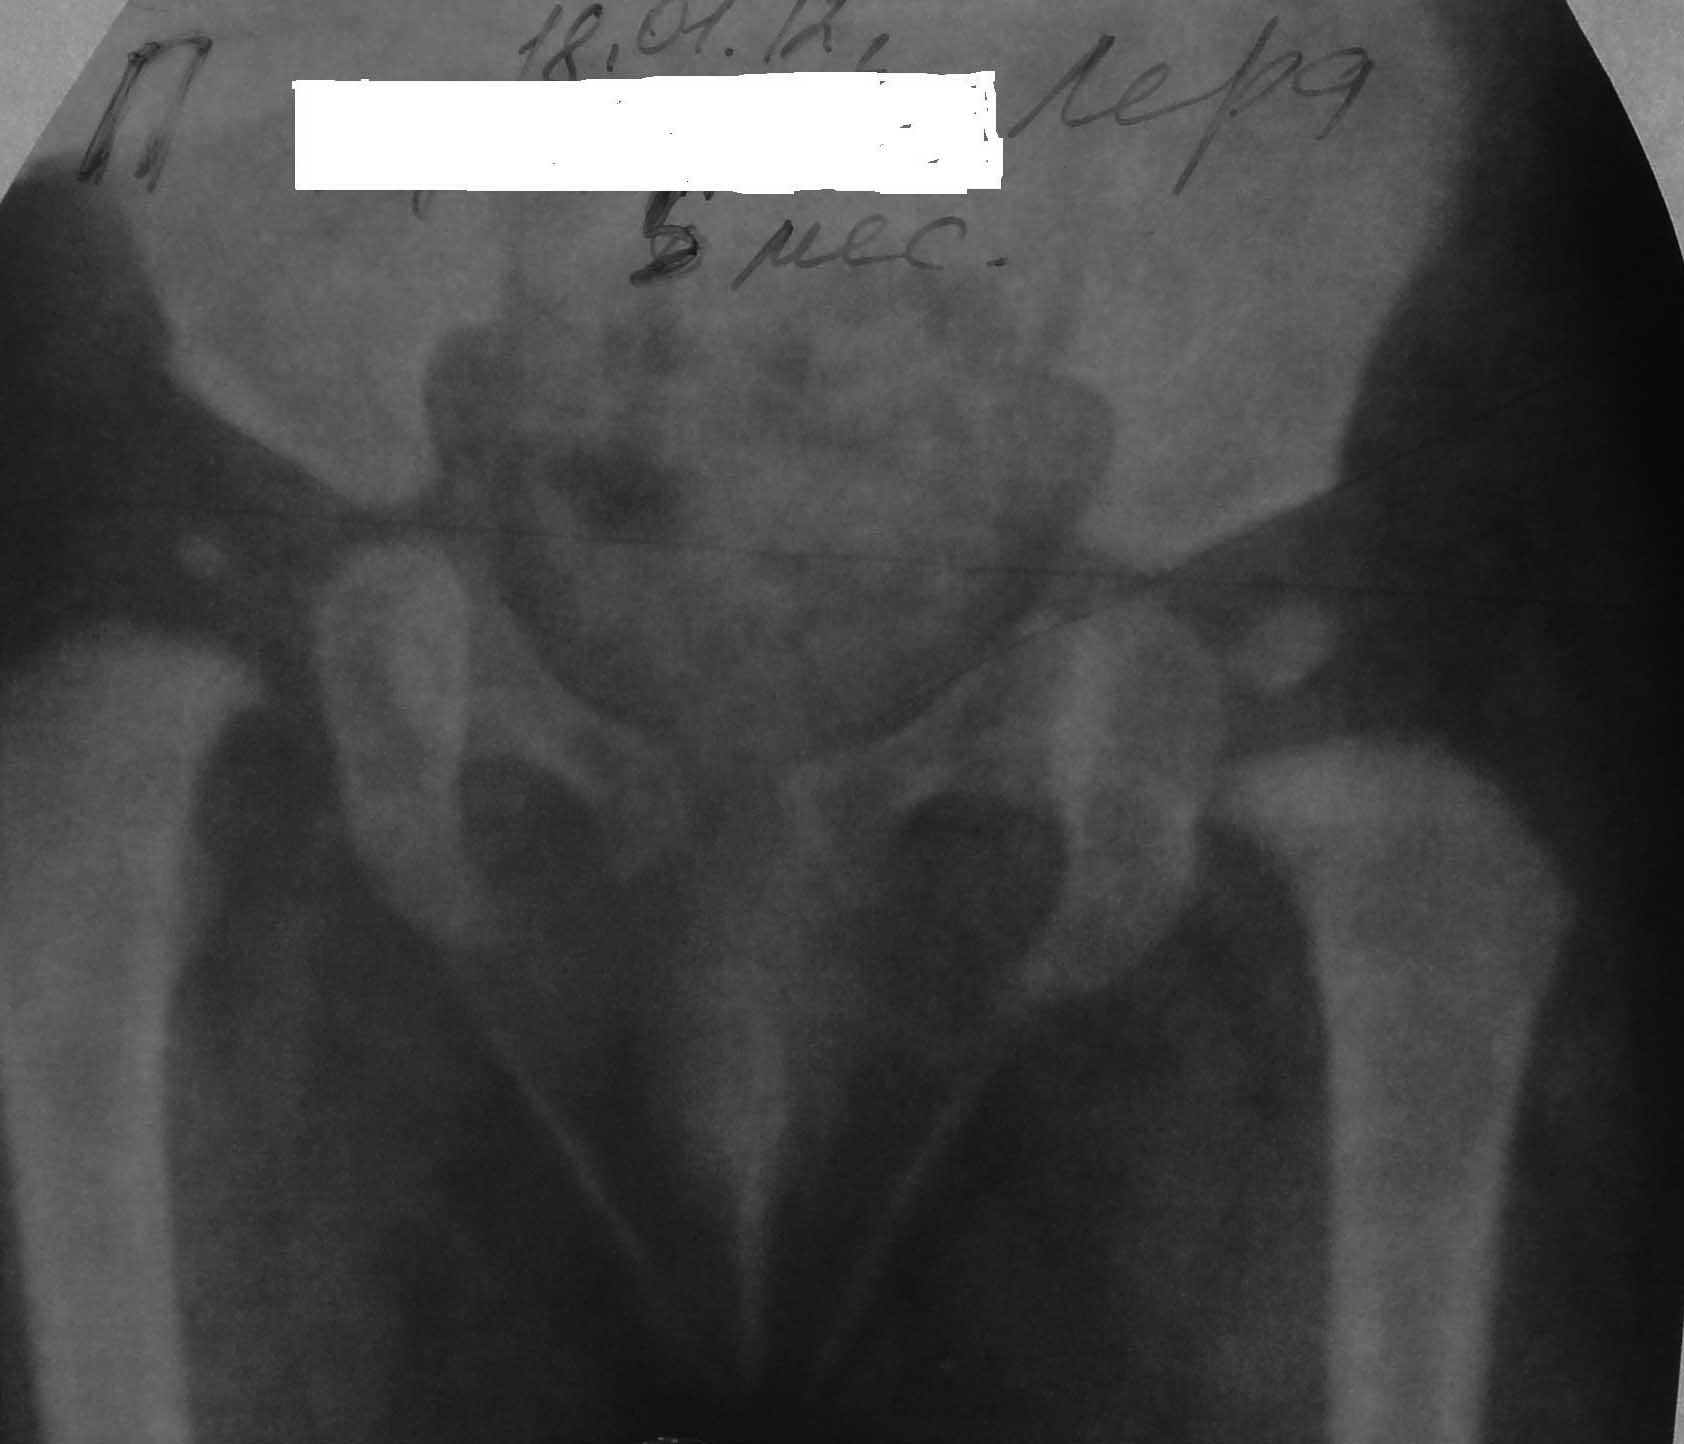

Ребенок моих знакомых девочка 6мес. от первой беременности первых родов, родила в срок, доношенная, маму беспокоила асимметрия бедренных складок, обратились ко мне.

Объективно ребенок правильного телосложения, движения в конечностях в полном объёме, длина нижних конечностей равная, дополнительная кожная складка на правом бедре, небольшая асимметрия половой щели, асимметрия ягодичных складок, отведение в т/б суставах удовлетворительное, справа несколько в меньшем объёме. Рекомендовал рентгенографию. Вот такая ситуация, ваше мнение по тактике лечения?

Создается впечатление о дисплазии правого т/бедренного сустава. УЗИ?

Скорее дисплазия , головки стоят на своих местах.

Ребенок уже большой да и рентген более информативен. Имеется дисплазия тазобедренных суставов, головка справа подвывихнута, находится внутри впадины. В таком возрасте нет никакой возможности повлиять на развитие ацетабулум. Применять какие-то приспособления для вправления и удержания головки не необходимости. Если до возраста 6 мес без лечения не вывихнулась, значит, и не вывихнется. Так что оставьте ребенка в покое, пусть растет.

Ильдар Ф. Ахтямов 26 Январь 2012, 02:44

Однозначно дисплазия справа. Можно рекомендовать тепловые процедуры на поясничный отдел позвоночника и тазобедренные суставы. Эл.форез с папаверином на поясничный отдел и с хлористым кальцием на пр. ТБ. Ограничивать ребенка в передвижении нет смысла. Никаких шин не надевать. Массаж поясницы и ягодичных мышц. Ежегодный рентгеноконтроль. Ситуация с перспективами развития сустава будет ясна к 1.5 - 2-х летнему возрасту.АИФ

Ne uveren chto sprava dysplasia:acetabular angle 27 degrees, Shenton and Perkins lines are normal.

АИ с обеих сторон одинаковый - 28 гр,

центрация шейки бедра по-Садофьевой с обеих сторон в пределах внутренней четверти...

До года это вариант нормы....

ИМХО дисплазии здесь скорее всего нет...

В том числе при сопоставлении с клиникой (асимметрия ягодичных складок неинформативно, некоторое ограничение отведения бедра с одной стороны - если это не техническая

ошибка - то бывает и в норме)

В данном случае ИМХО необходимо УЗИ, чтобы дополнительно подтвердить, что это действительно

вариант нормы...

У ребенка дисплазия тазобедренного сустава справа.

Линия Шэнтона нарушена (Shenton’s line) Ядро окостенения головки бедренной кости отстает в развитии.

В плане лечения: Отводящая шина и рентген контроль через 3 мес.